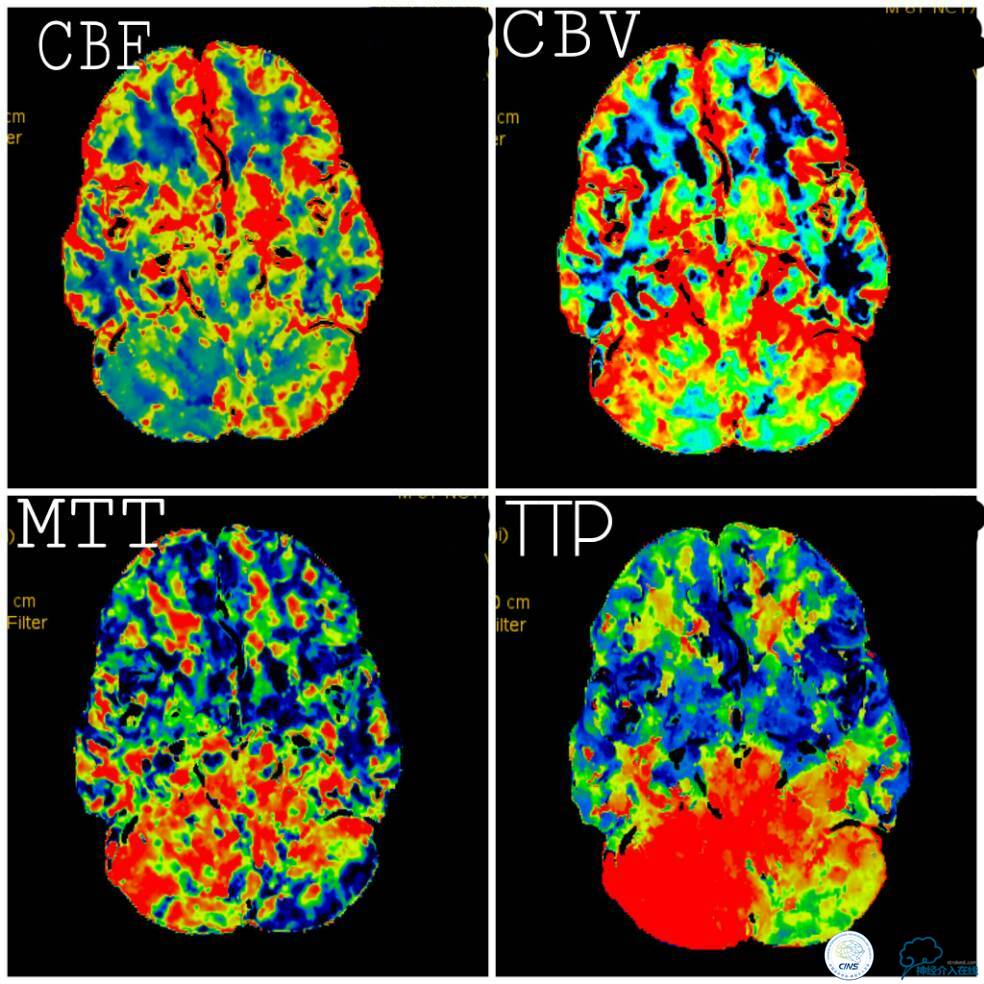

血栓弹力图检查:AA抑制率98.2%、ADP抑制率47.7%。颅内CTA及后循环CT灌注检查提示:右椎动脉V4段未见显影,左椎动脉与基底动脉汇合处重度狭窄,右椎动脉V4段在汇合点以下有显影(图5);双侧小脑半球低灌注,右侧为著(图6)。